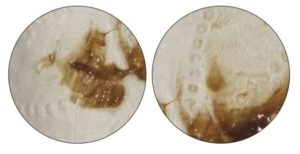

Для начала следует напомнить, что собой представляет эндометриоз. Суть этого заболевания заключается в патологическом разрастании внутреннего слоя матки (эндометрия) вне естественных пределов этого слоя. Например, поражаться могут фаллопиевы трубы, яичники, шейка матки, ткани влагалища, брюшная полость, мочевой пузырь и т.д. На фото вы можете увидеть, как выглядят очаги эндометриоза.